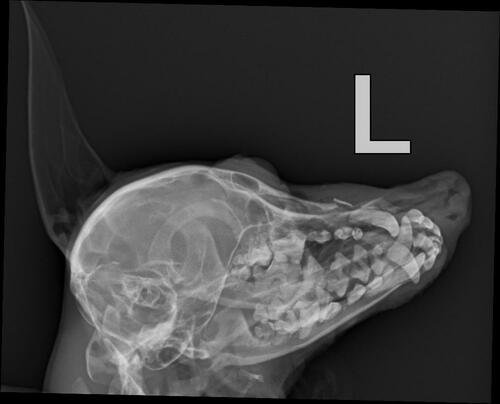

Eu sou Adriana tutora cadelinha Pirradia, que fOi atacada por um Pit Bul e está com fragmento ósseo da fratura nasal, visto após Ex de RX com laudo.

Valor da cirugia 2.500,00 a 3.000,00.